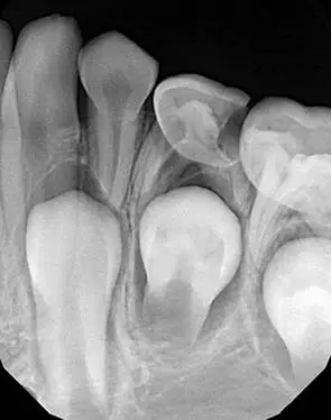

小牙片

X光拍片为什么要等小朋友看牙为什么要拍片?_https://www.jmylbn.com_新闻资讯_第9张

以检查单颗牙齿为目的,一般图像上可显示2~4颗牙齿,能观察到牙根的情况,所以牙医们要检查单颗牙齿时,往往会选择拍摄小牙片(但是对于小朋友来说,拍摄难度比拍摄全景片大)。